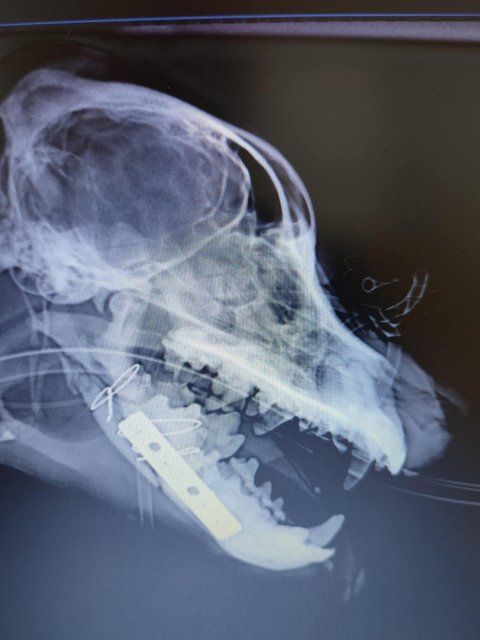

Röntgenbilder zeigten das Ausmaß der Zerstörung des Unterkiefers und den Bruch eines Beines.

Dieser Hund muss grausame Schmerzen haben, Zähne sind aus der Verankerung gerissen und sein Gesichtsschädel ist nicht mehr symmetrisch. Ein großes Stück des Unterkiefers ist komplett abgebrochen.

Camush Kopf ist wieder symmetrisch, der Kiefer wird jetzt mit Platte und Verdrahtung zusammengehalten und ein paar Zähne fehlen jetzt.

Sein Beinbruch ist ein offener Unterarmbruch von Elle und Speiche, der noch nach Erstversorgung operiert werden muss.